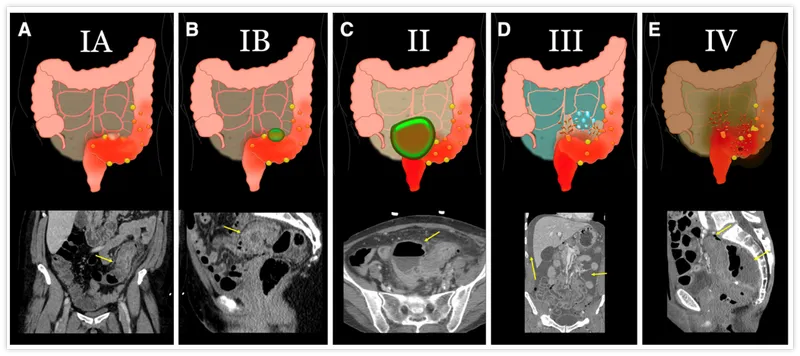

- Complicated Diverticulitis: Management guided by Hinchey Classification.

- Hinchey Stage I (Pericolic/mesenteric abscess):

- Small abscess (<4cm): IV antibiotics.

- Large abscess (≥4cm): Percutaneous drainage + IV antibiotics.

- Hinchey Stage II (Walled-off pelvic/distant intra-abdominal abscess): Percutaneous drainage + IV antibiotics.

- Hinchey Stage III (Generalized purulent peritonitis): Emergency surgery - Resection and primary anastomosis (R&A) if stable, or Hartmann's procedure.

- Hinchey Stage IV (Generalized fecal peritonitis): Emergency surgery - Hartmann's procedure.

- Hinchey classification guides management of perforated diverticulitis.